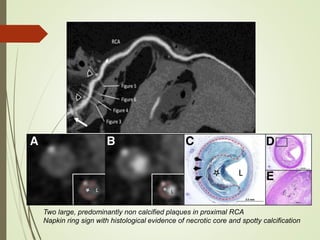

• Napkin ring sign- refers to specific CT feature of plaque

with large necrotic core and represents reliable marker of

plaque instability,

• Qualitative plaque feature defined in a non calcified plaque

cross section by two features:

1. Central area of low CT attenuation that is apparantly in

contact with lumen.

2. Ring like higher attenuation plaque tissue surrounding

this central area.

Two large, predominantly non calcified plaques in proximal RCA

Napkin ring sign with histological evidence of necrotic core and spotty calcification